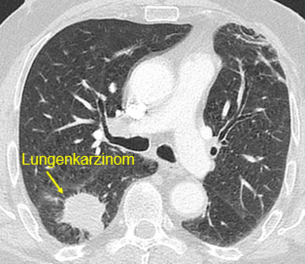

Lungenkrebs – Diagnostik, Verlauf und interdisziplinäre Abstimmung

Die Computertomographie (CT) ist die zentrale Untersuchung bei Verdacht auf Lungenkrebs, zur Stadieneinteilung und Verlaufsbeurteilung sowie für die Therapieplanung. Bei auffälligen Befunden wird das weitere Vorgehen interdisziplinär abgestimmt. Weitere Informationen finden sie außerdem auf den Seiten unseres Lungenkrebszentrums.

Beispielhafte Aufnahmen verschiedener Erkrankungen

(Lungenklinik Lostau)